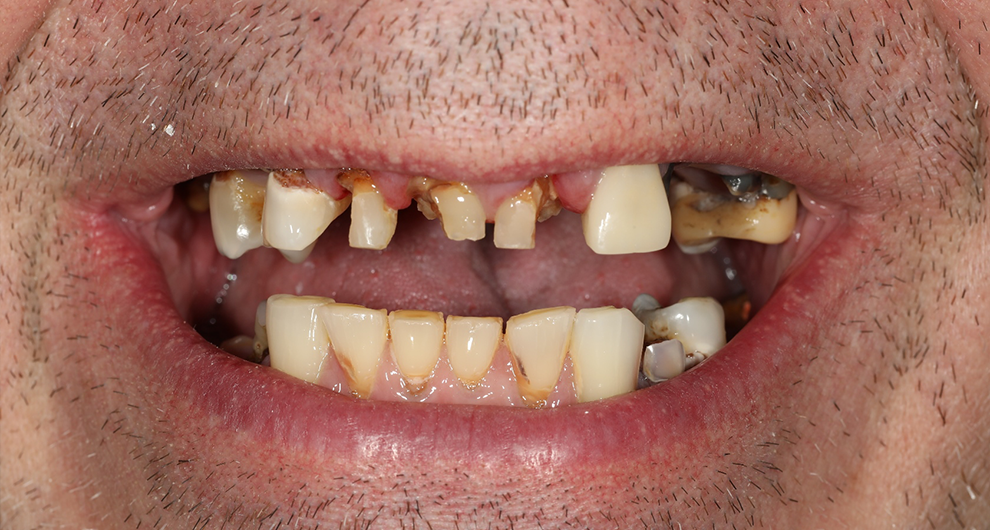

Click and drag the lines to reveal before and after

Before treatment After treatment

Before treatment

After treatment